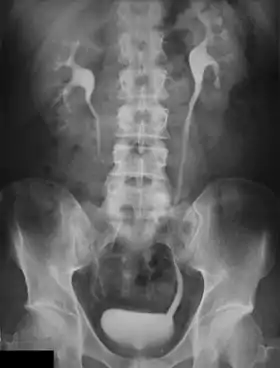

An intravenous pyelogram (IVP), also called an intravenous urogram (IVU), is a radiological procedure used to visualize abnormalities of the urinary system, including the kidneys, ureters, and bladder. Unlike a kidneys, ureters, and bladder x-ray (KUB), which is a plain (that is, noncontrast) radiograph, an IVP uses contrast to highlight the urinary tract.

In IVP, the contrast agent is given through a vein (intravenously), allowed to be cleared by the kidneys and excreted through the urinary tract as part of the urine.[5] If this is contraindicated for some reason, a retrograde pyelogram, with the contrast flowing upstream, can be done instead.

An injection of X-ray contrast medium is given to a patient via a needle or cannula into the vein,[7] typically in the antecubital fossa of arm. The contrast is excreted or removed from the bloodstream via the kidneys, and the contrast media becomes visible on X-rays almost immediately after injection. X-rays are taken at specific time intervals to capture the contrast as it travels through the different parts of the urinary system.[7] At the end of the test, a person is asked to pass urine and a final X-ray is taken.[7]

Normal appearances

Immediately after the contrast is administered, it appears on an X-ray as a 'renal blush'. This is the contrast being filtered through the cortex. At an interval of 3 minutes, the renal blush is still evident (to a lesser extent) but the calyces and renal pelvis are now visible. At 9 to 13 minutes the contrast begins to empty into the ureters and travel to the bladder which has now begun to fill. To visualize the bladder correctly, a post micturition X-ray is taken, so that the bulk of the contrast (which can mask a pathology) is emptied.